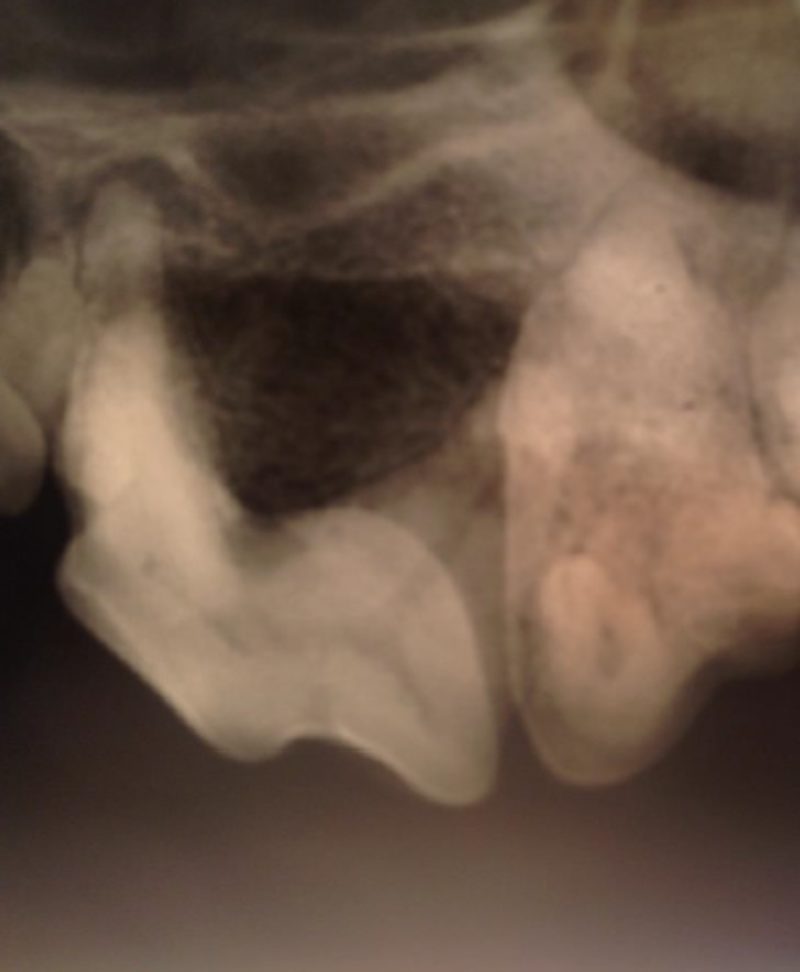

Vor der Extraktion der Zähne ist es unerlässlich, sich mittels Röntgenbildern einen genauen Überblick über den Zustand der Zahnwurzeln und des umgebenden Kieferknochens zu verschaffen, um die Extraktion auch sicher durchführen zu können. Dies gelingt mit intraoralen Einzelzahnaufnahmen, die mit einem speziellen Dentalröntgengerät angefertigt werden.

Bei Betty war röntgenologisch eine deutliche Entzündung der Wurzelspitzen zu sehen. Diese Wurzeln sind besonders fragil, so dass bei einer Extraktion sehr vorsichtig gearbeitet werden muss, damit sie nicht abbrechen. Bei der Extraktion der Oberkieferreißzähne ist zu beachten, dass diese drei Wurzeln besitzen. Der Zahn muss also mit einem speziellen Bohrer oder Trennscheibe in drei einzelne Teile zerteilt werden und zwar so, dass danach zu jeder Wurzel ein gerader Zugang von der Maulhöhle aus besteht. Dann kann jede Wurzel einzeln mit speziellem Instrumentarium zunächst vorsichtig gelockert und schließlich extrahiert werden. Nach der Extraktion der Zähne konnte man auch mit bloßem Auge die schweren Schäden, die die Entzündung angerichtet hatte, an den Wurzeln erkennen.